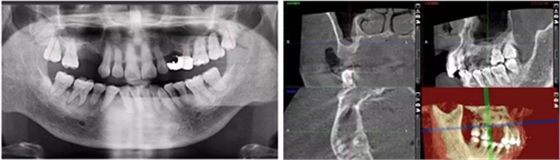

術(shù)后當(dāng)天 術(shù)后7個月